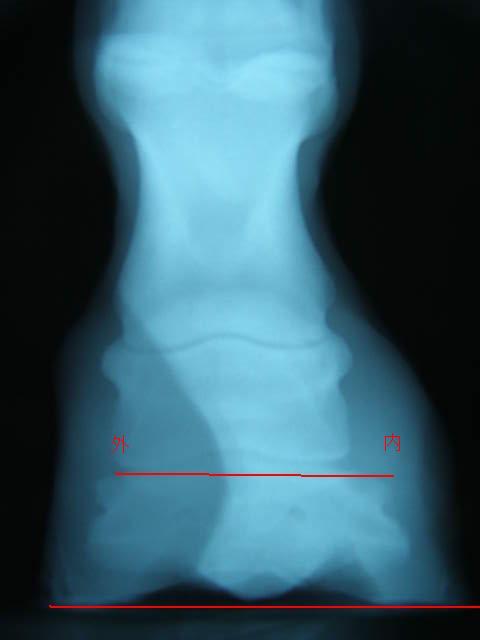

9月の左前肢

ラメラーウェッジがだいぶ取り除かれ、蹄が蹄壁にきちんとくっついて生えてきているのが確認できてホッとしました。

9月の右前肢